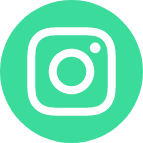

آنوریسم مغزی برآمدگی در یک رگ خونی در مغز است که میتواند باعث خونریزی مغزی در نتیجه نشت یا پارگی شود. این وضعیت نیاز به مراقبت فوری پزشکی دارد زیرا زندگی بیمار را تهدید میکند. آیا آنوریسم مغزی باعث مرگ میشود؟ پارگی آنوریسم سریعاً تهدیدکننده زندگی است و نیاز...